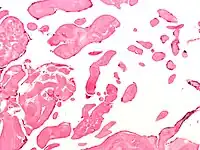

| Low magnification micrograph of an excised aortic valve papillary fibroelastoma showing the characteristic avascular branching papillae, H&E stain | |

Papillary fibroelastoma are typically found and accurately diagnosed by imaging. The diagnosis is confirmed by pathology. Histologically, papillary fibroelastomas have branching avascular papillae, composed of collagen, that are covered by endothelium.